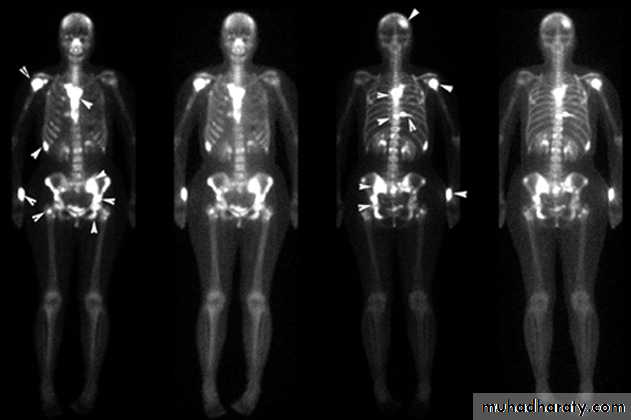

(3) Blood streams: it is by this route skeletal metastases occur. In order of the frequency the lumbar vertebrae, femur, thoracic vertebrae, rib and skull are affected and these deposits are generally osteolytic. Metastases may also commonly occur in the liver, lung, brain, and occasionally adrenal glands and ovaries.

This is described as cancer en-cuirasses when disease progress around chest wall. About 5% carcinoma in UK presented as locally advanced or symptoms of metastatic disease this figure is much higher in developing countries. These patients under goes staging evaluation so this will include a careful clinical examination, chest x-ray, CT scan chest and abdomen and isotope scan, bone scan.